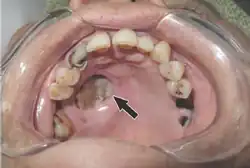

Should the fungus deposit in the nose or sinus and extend to brain, symptoms and signs may include one-sided face pain or headache.[7] There can be numbness, fever, loss of smell, a blocked nose or runny nose.[7] The person may appear to have sinusitis.[23] The face may look swollen on one side, with rapidly progressing "black lesions" across the nose or upper inside of mouth. One eye may look swollen and bulging, and vision may be blurred.[5][23][24]

Fever, cough, chest pain, and difficulty breathing, or coughing up blood, can occur when the lungs are involved.[5] A tummy ache, nausea, vomiting and bleeding can occur when the gastrointestinal tract is involved.[5][25] Affected skin may appear as a dusky reddish tender patch with a darkening centre due to tissue death.[26] There may be an ulcer and it can be very painful.[4][6][26]

Tissue destruction of inside upper mouth